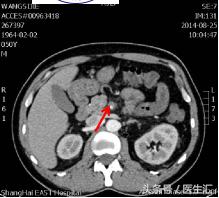

到晚上9:30的时候,患者又出现上腹部腹痛,而且腹痛呈持续性,伴恶心呕吐2次,呕吐呈非喷射状,呕吐物为胃内容物,解黄色水样便一次。夜班医生给与耐信(埃索美拉唑钠)抑酸,得舒特(匹维溴铵)解痉治疗,腹痛不能缓解。再次复查电解质+淀粉酶正常;血常规白细胞和中性粒细胞增高,其他正常。结合患者腹痛、恶心呕吐、水样便,症状很像急性胃肠炎,所以给与左氧氟沙星(左克)抗炎治疗,同时用654-2解痉等治疗。但是患者持续性腹痛没有明显缓解,第7天凌晨2:00夜班医生查体全腹部平软,但是上腹部有一点点轻压痛,无反跳痛,麦氏点无压痛,夜班医师给与654-2解痉处理,但是效果还是不满意。所以做了一个中上腹CT平扫示:肠系膜上动、静脉周围渗出性改变,建议增强扫描。

第7天凌晨2:00夜班医生查体全腹部平软,但是上腹部有一点点轻压痛,无反跳痛,麦氏点无压痛,夜班医师给与654-2解痉处理,但是效果还是不满意。所以做了一个中上腹CT平扫示:肠系膜上动、静脉周围渗出性改变,建议增强扫描。第7天早上10:00做中上腹增强CT示:肠系膜上动脉内低密度影,考虑附壁血栓形成,局部管腔重度狭窄。这个时候这个患者的诊断应该来说已经很明确了。于是请了相关科室的医生进行会诊,决定进行经皮选择性肠系膜动脉造影+肠系膜动脉溶栓术。患者溶栓导管行脉冲式注射尿激酶溶栓,患者术后24h出现便血4次,200ml/次。